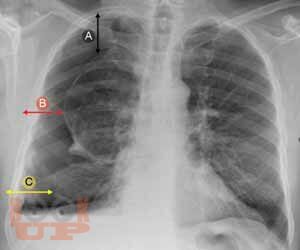

First textbook about pleural disease written and edited by Indian authors. First pleural textbook which has contributions from multiple authors. Textbook of pleural disease which has been authored by multiple specialtiesa unique feature where each chapter has been written by the concerned specialists, e.g., pleural disease in kidney disease by nephrologist, hepatic hydrothorax by hepatologist, and pleural disease in gynecological disorder by gynecologist. Every aspect of pleura from embryology, anatomy, physiology, and radiological diagnosis has been covered in detail. Role of ultrasonography in pleura, which is now a vital tool for point-of-care management has been described in detail. High-quality pleural imaging and its highlights are shown in concerned chapters Pathophysiologic basis of pleural diseases has been discussed with each specific disease. Concise algorithm summarizing disease management has been clearly depicted. Updated treatment as per recent guidelines has been incorporated. The topics in pleural diseases have been written by eminent chest physicians all over India. A special chapter describes pleural diseases in COVID, in the post pandemic era. Being a Lung Transplant center, a special chapter on overview on pleura issues in lung transplant has been elaborated.